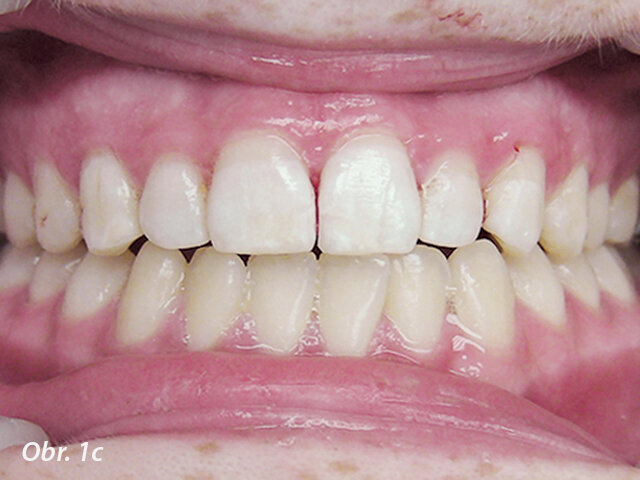

Obr. 1b, c: Po připojení obou fragmentů byl podél lomné linie vybroušen oblý schůdek, doplněn dalším kompozitem a zpolymerován na místě. To zvýší sílu spojení a lépe zakryje lomnou linii.

První, co je třeba udělat u jakékoliv korunkové nebo korunko-kořenové fraktury, je pokusit se najít odlomený fragment zubu. S moderní bondovací technologií je možné znovu spojit odlomený fragment se zbytkem zubu, což je esteticky nejlepší řešení. Ještě před připojením fragmentu zubu musí být tloušťka vrstvy zubu mezi pulpou a povrchem zhodnocena radiologicky a klinicky. Pokud zbývá alespoň 0,5 mm dentinu, není nutno místo překrývat ochrannou podložkou. Pokud je stanoveno, že zbytkový dentin je méně než 0,5 mm široký, je doporučeno překrýt oblast fraktury nejblíže u pulpy podložkou a tvarově přizpůsobit spojovací plochu fragmentu. Pokud byl fragment zubu držen v suchu, měl by být rehydratován v destilované vodě nebo slině po dobu 30 minut před spojováním, což zvýší vazebnou sílu (obr. 1a–c).